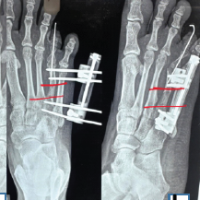

A standard volar approach was made over the flexor carpi radialis (FCR) tendon. Two separate intra-articular fragments were identified: A radial styloid component and a lunate facet component. A volar distal radius locking plate was used to provide primary fixation. The patient was placed in a volar-based splint. During the same anesthesia event, the patient underwent operative fixation of pelvis fractures as well. The patient was compliant with physical therapy protocols for distal radius fracture and pelvis fractures. Five months after the index injury, the patient presented to the orthopedic trauma clinic with acute inability to flex the right thumb without an inciting event. The patient was subsequently referred to the senior author for further management. Radiographs at that time revealed a well-healed distal radius fracture with plate placement on the volar rim (Fig. 2). Examination revealed inability to flex the thumb IP joint, with a lack of tenodesis effect, which confirmed atraumatic FPL rupture. Treatment options were discussed, and the patient elected to undergo removal of hardware and FPL tendon reconstruction with PL interpositional graft. The operation began with a standard volar approach over the FCR tendon. The proximal FPL tendon stump was found to be completely ruptured and the surrounding tenosynovium was sharply excised. There was an excellent excursion of the proximal FPL muscle belly, which was found to be >2 cm. The median nerve was found to be adherent to the FPL and was subsequently neurolyzed. The previously placed plate and screws were removed and fluoroscopic imaging confirmed a well-healed fracture. An incision was made over the thumb in a Brunner-like fashion. The A1 pulley was released. The distal FPL tendon stump was then pulled through the wound (Fig. 3). A 15 cm length of PL tendon was harvested. The PL tendon autograft was secured using a Pulvertaft weave technique into the distal portion of the FPL tendon and reinforced with 3-0 braided polyester suture (Fig. 4). The tendon was delivered through the palm and out through the forearm incision. The wrist was held in neutral position while appropriate tension was placed and a first proximal Pulvertaft weave was placed. The wrist was taken through a full range of motion and appropriate tension was confirmed (Fig. 5). The thumb maintained 5° of flexion with full wrist flexion. The patient was placed in a thumb-based dorsal blocking splint and made non-weight bearing with the right upper extremity.